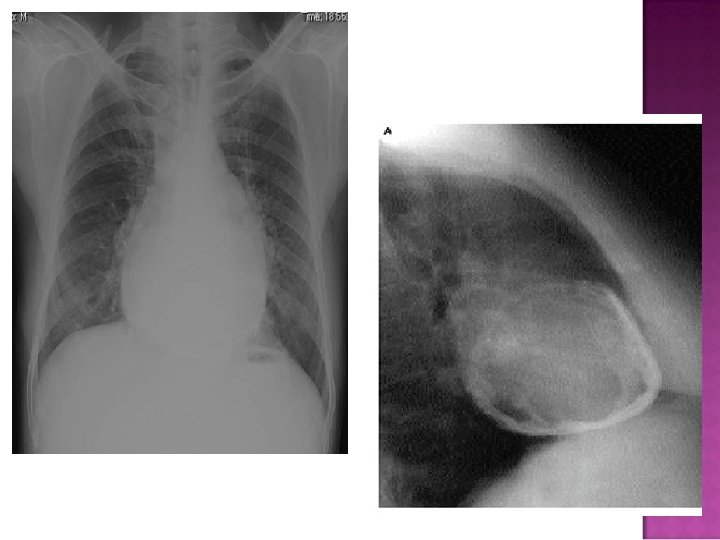

Cardiomegaly due to a massive pericardial effusion. At least 200 m. L of pericardial fluid must accumulate before the cardiac silhouette enlarges.

� Sudden inc in size of cardiac silhouette w/o specific chamber enlargement � Effacement of the normal cardiac borders � Development of a “flask” or “H 2 O-bottle” shaped heart

Normal in patients with acute pericarditis unless pericardial effusion is present Enlarged cardiac silhouette Requires 200 cc of fluid